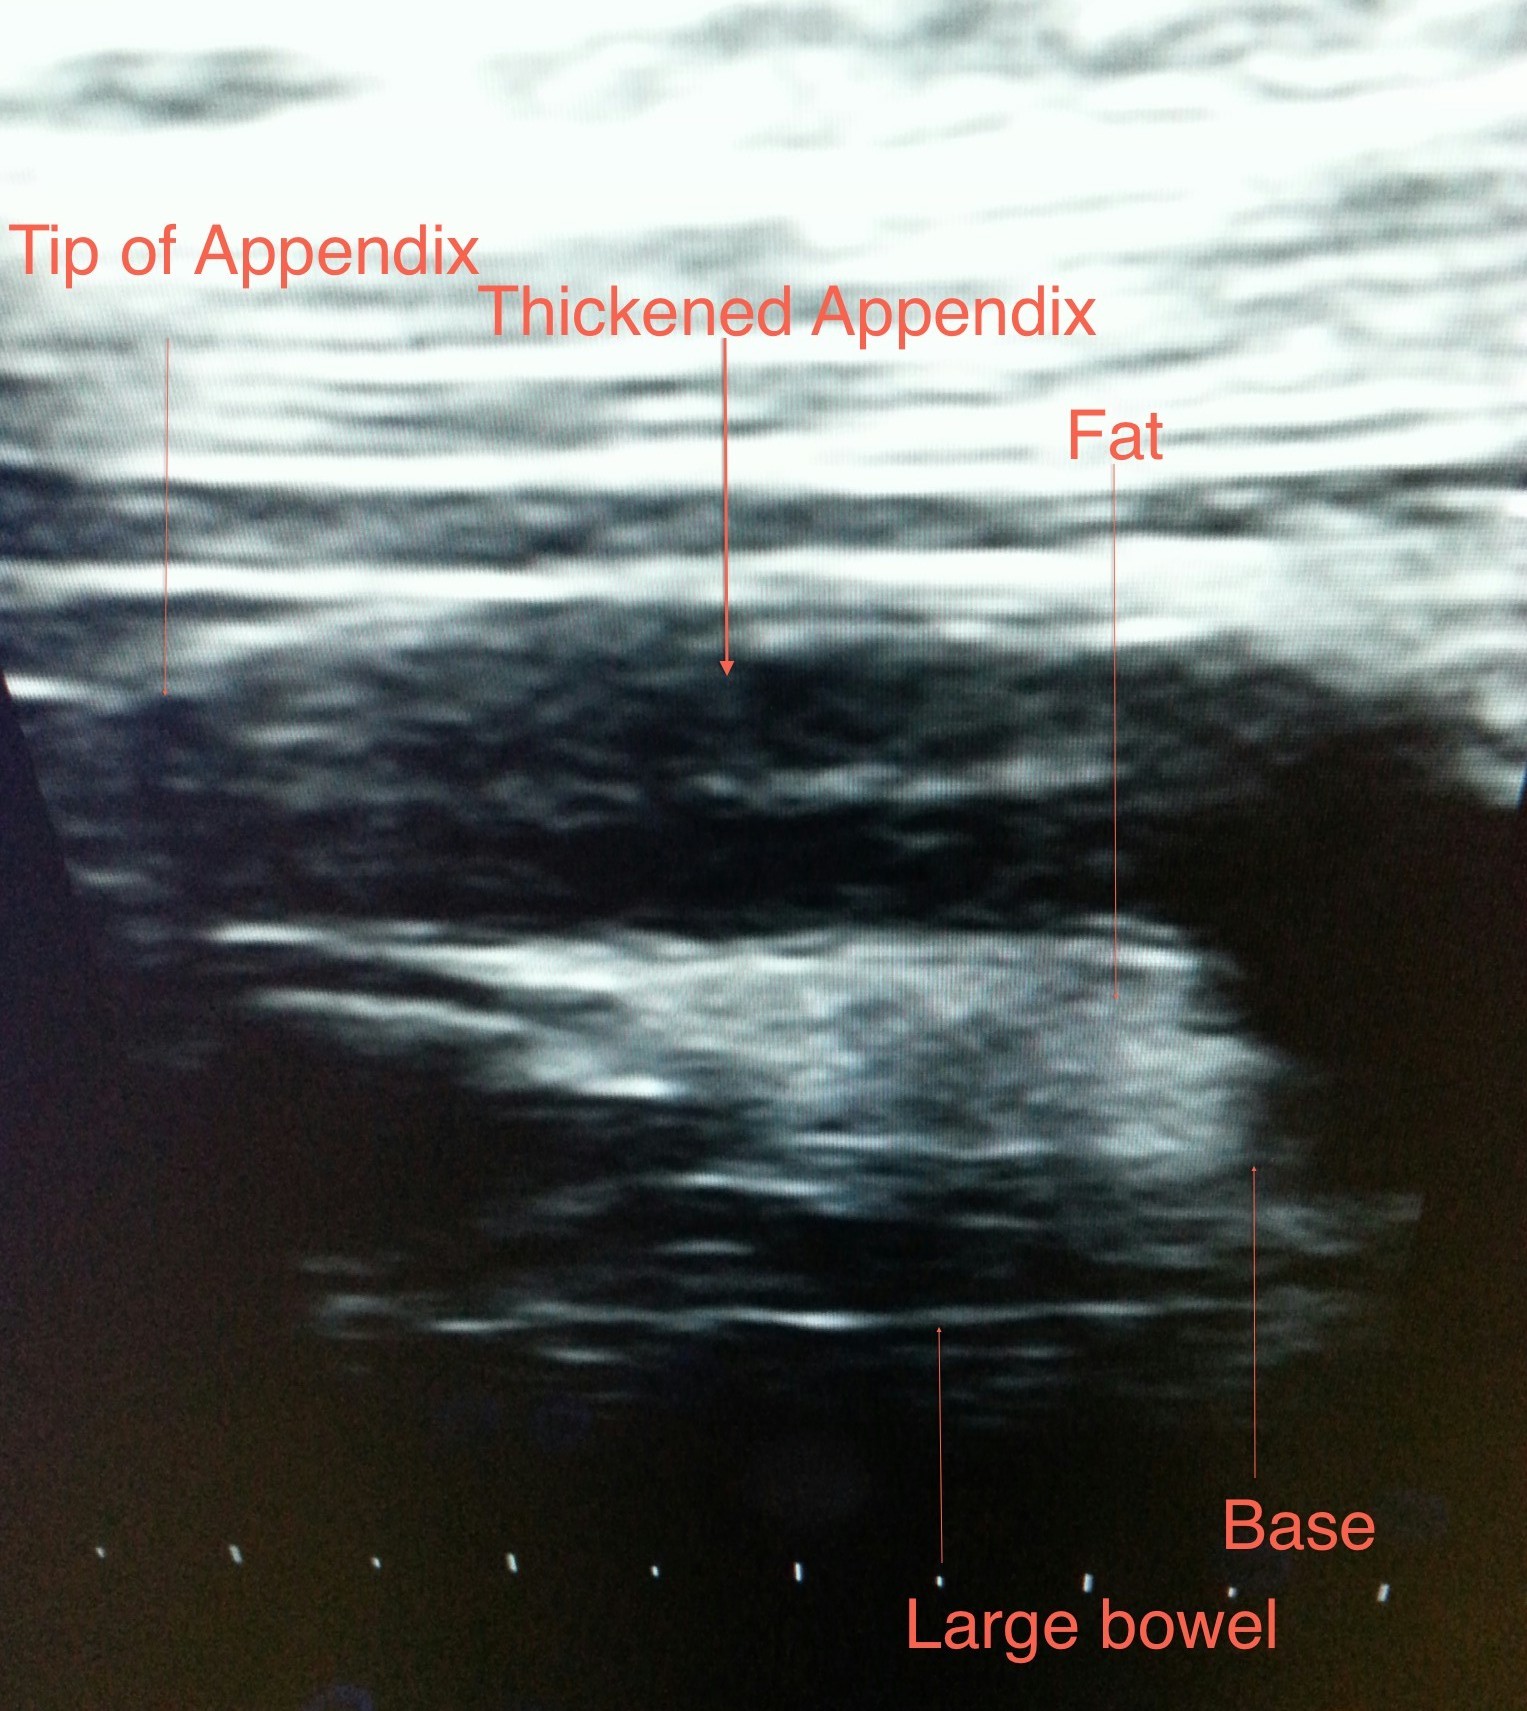

Appendicitis: Appendix is a normal organ seen in right lower abdomen. When it is thickened due to infection or obstruction it is called appendicitis. So when one has disease of appendix he/she has “appendicitis” and not “appendix”. Appendicitis is suspected(diagnosed)on the basis of findings observed and elicited by doctor along with few blood (laboratory)investigations. To confirm the clinical (by history given by the patient and doctor’s examination)diagnosis ultrasound is used. On some occasions ultrasound will not succeed in demonstrating the abnormal appendix and these are the situations which warrant a CT scan. To exclude a diagnosis of appendicitis CT is recommended.